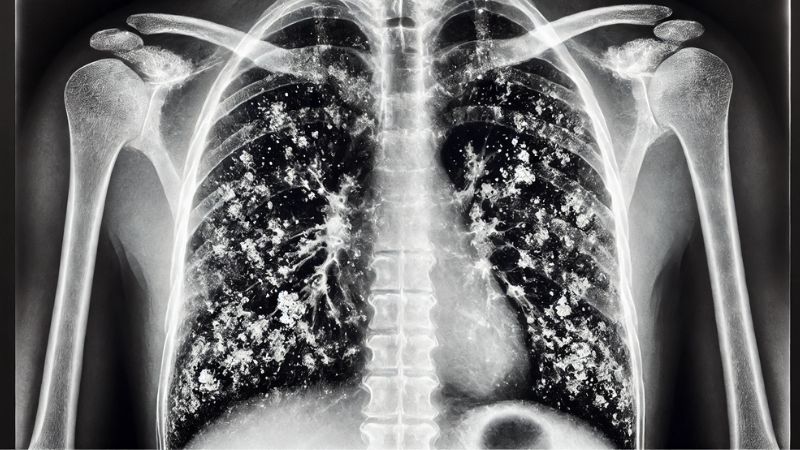

Tiền sử tiếp xúc với Amiăng và nghề nghiệp, môi trường là các yếu tố quan trọng giúp chẩn đoán bệnh bụi phổi Amiăng . Ngoài ra, một số xét nghiệm có thể được chỉ định để xác định mức độ tổn thương phổi như:[3]

- Chụp X-quang lồng ngực.

- Chụp cắt lớp vi tính ngực (CT-scan ngực).

Các xét nghiệm hình ảnh giúp chẩn đoán mức độ xơ hóa phổi